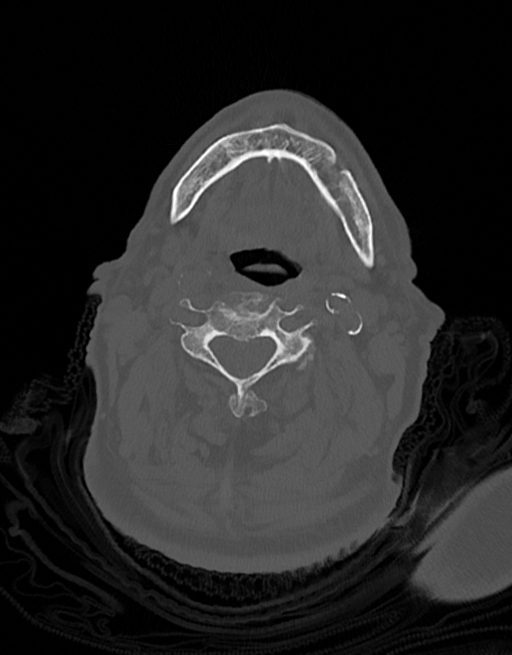

در سي تي اسکن اسپيرال نازو فارنکس با و بدون کنتراست (مولتي ديدکتور 16 با مقاطع ظريف و بازسازي هاي ساژيتال و کرونال):

– توده نسج نرمي به ابعاد mm 40 x 45 x 60 در ناحيه پاروتيد راست، با enhancement هتروژن پس از تزريق کنتراست مشهود است که مطرح کننده آدنوم پاروتيد مي باشد.

– شواهدي از تهاجم توده به استخوان و عروق اطراف مشهود نيست .

– کلسيفيکاسيون در ديواره شريان هاي کاروتيد دو طرف مشهود است .

– بررسي بافتي توده پاروتيد راست پيشنهاد مي شود .